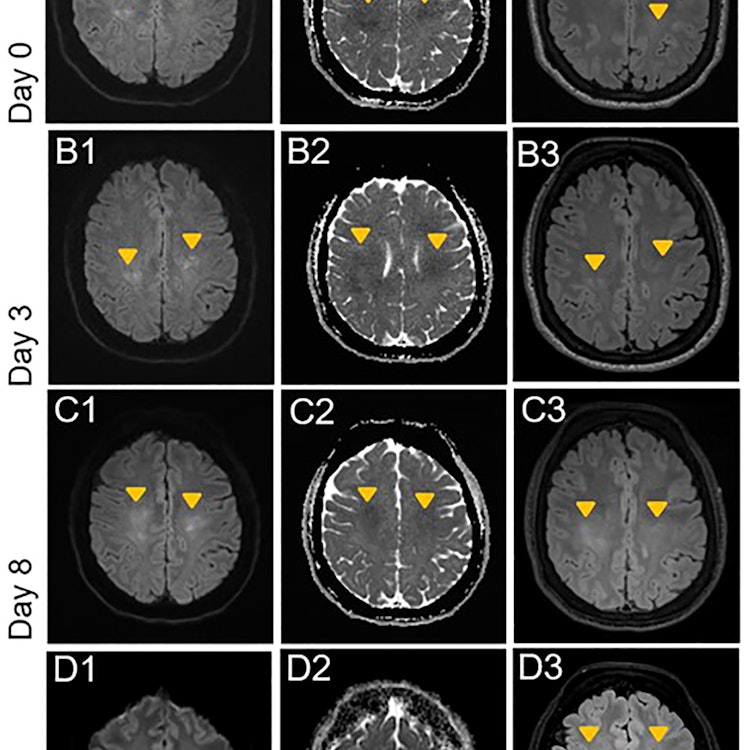

Objectives: Daratumumab, a monoclonal antibody against CD38, is increasingly used in the treatment of multiple myeloma, other hematological malignancies and autoimmune diseases. Little is known about its CNS toxicity. We present a case of a patient with POEMS syndrome (syndrome of polyneuropathy, organomegaly, endocrinopathy, monoclonal gammopathy and skin changes) who developed an acute leukoencephalopathy shortly after initiation of therapy with daratumumab. Methods: Case report following the CARE case report guidelines Results: The patient presented with symptoms of headache and diffuse worsening of a pre-existing tetraparesis. MRI showed a rapidly progressive leukoencephalopathy. Extensive diagnostic evaluation revealed no specific cause, suggesting the leukoencephalopathy to be caused by daratumumab. Discussion: Our report highlights a probably rare, but clinically significant adverse effect of daratumumab and underlines the necessity of raised vigilance for neurological side effects in patients treated with daratumumab.